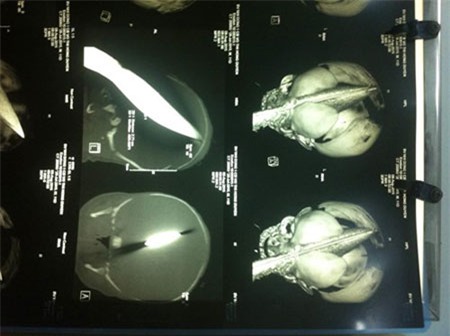

Kết quả chụp CT cho thấy bé bị dao đâm từ hốc mắt trái xuyên qua não phải, thấu ra tận phía sau, dao bầu cắm sâu tới 11cm vào trán.

Lo ngại bệnh nhi có thể đột tử bất cứ lúc nào vì có tiền sử viêm phổi đi kèm nên các bác sĩ của Bệnh viện Nhi Đồng 1 đã quyết định hội chẩn với Bệnh viện Nhân dân 115, khẩn trương phẫu thuật, lấy dao ra khỏi đầu cháu bé trong chiều 8/8.

Ca mổ lấy dao ra khỏi đầu thuận lợi nhưng y bác sĩ vẫn lo ngại bé bị chảy máu não và nguy cơ nhiễm trùng cao. Vậy nên cháu bé được điều trị phối hợp nhiều loại kháng sinh để ngừa nhiễm trùng não - màng não và viêm phổi, dùng thuốc vận mạch, giảm đau và được theo dõi rất chặt chẽ...